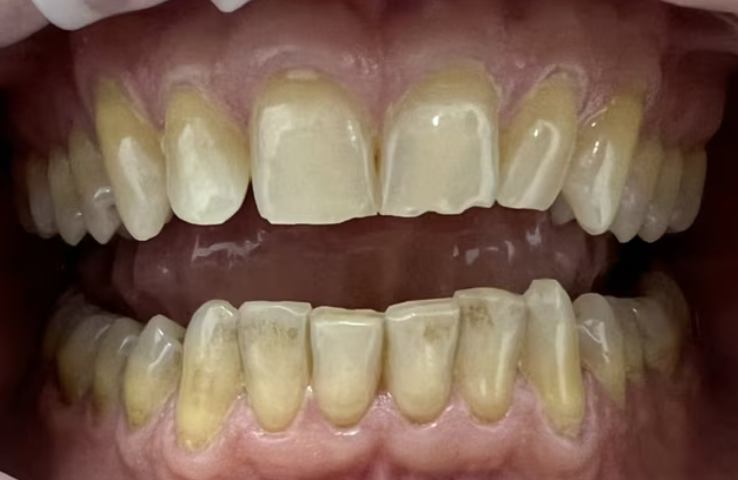

На странице представлено портфолио стоматологий Москвы с работами до и после профессиональной чистки зубов. В нашем портфолио собраны разные клинические случаи: от удаления незначительного налета до снятия массивного поддесневого камня. Здесь вы можете увидеть, как возвращается естественный цвет и внешний вид зубов после процедуры. Изучите результаты до и после чистки зубов, чтобы увидеть реальный эффект и выбрать клинику в Москве, где профессиональная гигиена поможет вернуть зубам здоровый вид.

Профгигиена

Пациентка проходит ортодонтическое лечение в нашей клинике. Регулярно приходит на профессиональную чистку.

Доктор: Гарибян Эдгар Артурович